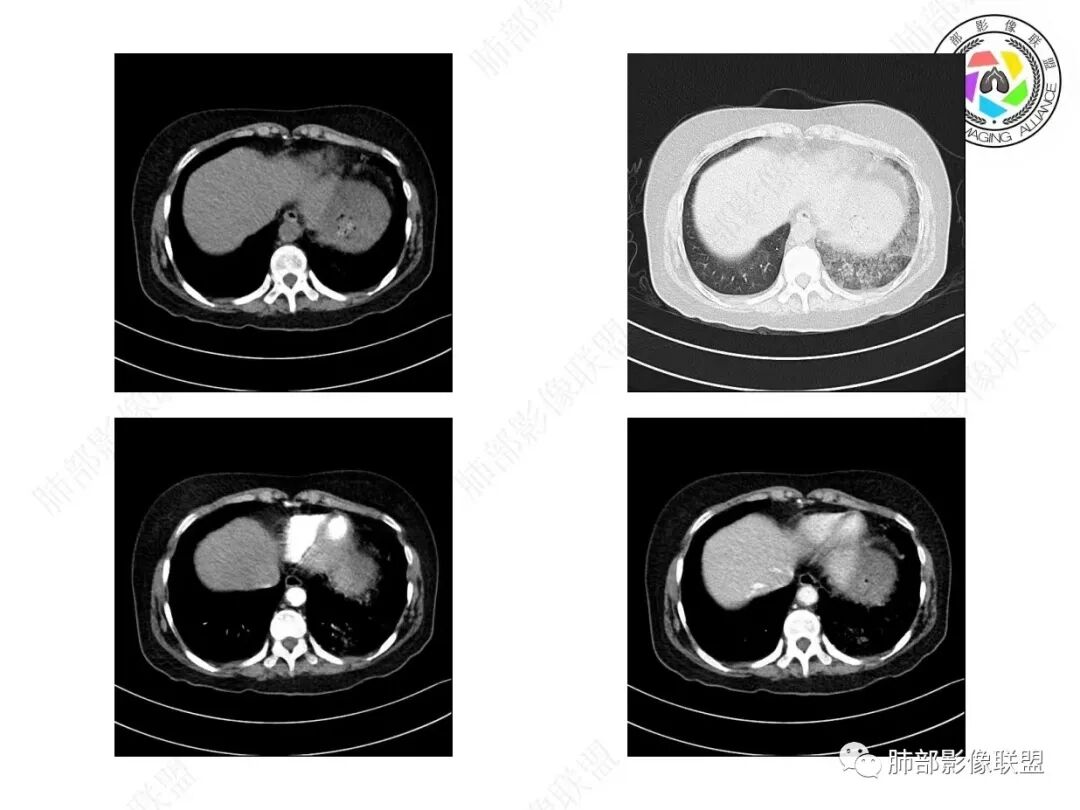

宇宙:两肺多发磨玻璃影,边缘模糊,左肺为著,左肺下叶伴实变,增强实变不均匀强化,其内支气管有阻塞、扩张,考虑粘液腺癌。

飞鹰行动:病史较长,左肺下叶实变及周围磨玻璃影,增强可见血管造影征,考虑左肺下叶粘液腺癌。

放射线:左肺下叶实变及双肺磨玻璃影,左下肺病灶周围磨玻璃影,有重力作用,呈叠瓦片状,增强可见血管造影征,考虑左肺下叶粘液腺癌伴双肺播散。

良孑:左下肺实变,边界似清非清,邻近肺野见腺泡样播散灶,强化见血管造影征,中年女性,咳白痰,病程一月,考虑粘液腺癌并肺内播散,鉴别吸入。

谢加平:中年女性,慢性干咳史,少量白色粘液痰,左肺下混合密度影,实性密度比胸壁软组织低,周围见大片磨玻璃密度,边缘模糊,叠瓦征分布,实边区内血管束边缘模糊(需重建血管束确认分支有无消失),余肺叶散在分布磨玻璃病灶(气道种植),抗炎治疗无效,左肺下叶符合肺炎型粘液腺Ca并双肺叶气道飘散转移!

患者,女性,57岁。咳嗽1月、咳痰4天,亚急性病史,抗炎效果不佳,体温不高,痰为白色黏痰,白细胞稍高,主病灶在左下叶,实变+GGO,其余肺也有GGO,伴随有结节。

本例病例老年女性,慢性病程,抗炎效果不佳。CT示左肺下叶实变影,周围可见大片磨玻璃密度影,密度不均。右肺亦见少量斑片状磨玻璃密度影。增强可见血管造影征,结合南大分析,排除真菌,结核等,答案就呼之欲出了。